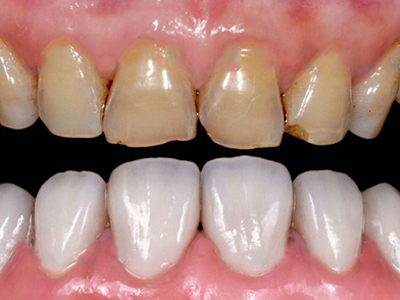

酸蚀症牙齿缺损不平整图

酸蚀症患者的牙齿会发生缺损,轻度时仅表现为牙齿尖端凹凸不平,有少量骨质缺失,缺损处有黄褐色至红褐色斑点,该病可能是长期接触外源性酸性物质而致病。

酸蚀症牙齿有黄斑图

酸蚀症可导致患者靠近牙根处有偏黄褐色的黄斑,形状不规则,质地较软,易崩碎而逐级形成实质性缺损,需保持口腔卫生,进行劳动保护。